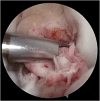

Graft-tunnel mismatch (GTM) is a known technical challenge that can occur with anterior cruciate ligament reconstruction when using a patellar tendon autograft. Two-incision anterior cruciate ligament reconstruction is a well-established technique with excellent outcomes and can serve as an excellent tool to prevent GTM. Traditionally, 2-incision femoral tunnel drilling has been performed using an over-the-top guide through a lateral incision, but more modern retrograde reamer guides can allow this to be done percutaneously. We detail how a minimally invasive 2-incision femoral tunnel drilling technique can be used in patients with patellar tendon lengths that are longer than average to avoid GTM.